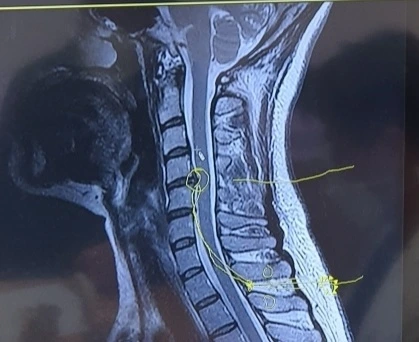

아침이 되어 엑스레이와 MRI를 통해 본 나의 목은 '거북목' 그 자체였고 여러 개의 디스크가 탈출해 있었다.

MRI로 본 나의 목상태

안 그래도 평소 직업적으로 컴퓨터를 쓸 일이 많아서 거북목이 되기 쉬운 자세를 많이 취하여 '거북목의 업보'를 한평생 많이 쌓아왔던 나인데, 육아를 하면서 목을 꺾어 아기를 자꾸 내려다보는 일이 많았고 무거운 아기를 어깨에 안은 것이 목에 많은 부담을 주었던 것 같다.